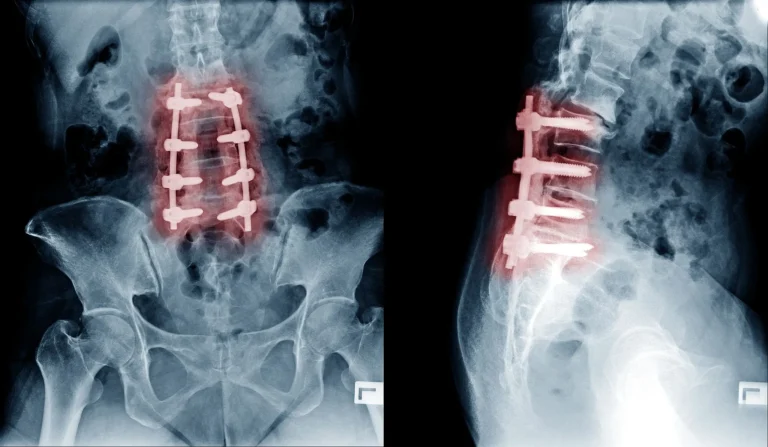

X-ray showing spinal fusion with metal implants in the lumbar region, both front and side views.

Back Pain Gets Worse

X-ray showing spinal fusion with metal screws and rods in the lower back.

Additional Surgery Likely Needed